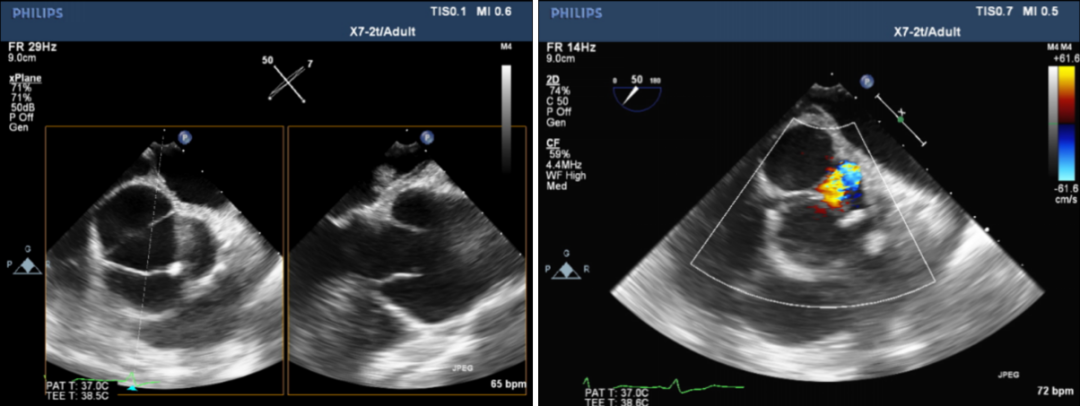

术前超声:

术前超声提示:

二叶式主动脉瓣(TYPE1)关闭不全并钙化;主动脉窦部瘤样增宽;左室大;主动脉硬化;主动脉瓣上血流速度加快,瓣下返流(大量)。

术后超声:

Vitaflow瓣膜位置良好,轻微瓣周漏